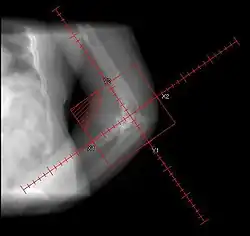

• Randomized. 161 patients. Preop RT 7/1 (<4 hours) vs. Postop RT 17.5/5 (<=96 hours). Portals periacetabular and intertrochanteric soft tissues

• Failure rate: radiological overall 11%; preop 19% vs. postop 5% (SS). Functional 14% Highest failure in pre-op RT for Brooker Grade III-IV (39%), otherwise preo-op and post-op outcomes comparable

• Conclusion: preop RT inferior to postop RT, except in Grade I-II, where no difference

• Randomized, multi-institutional. 98/122 patients with risk factors, following elective hip replacement. Treated with pre-op RT 7-8/1 <4 hours vs. post-op RT 7-8/1 <48 hours. Fields to soft tissues between periacetabular region of pelvis and intertrochanteric portion of femur. Median F/U 9.5 months

• Failure rate: radiographic preop 26% vs. postop 28% (NS); clinical 2% vs. 5% (NS)

• Conclusion: no difference between preop and postop